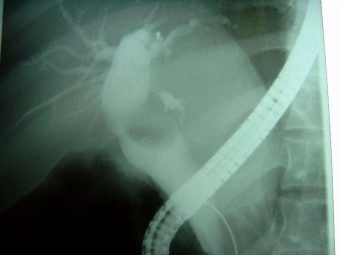

Cálculo gigante y divertículo duodenal ERCP

Envíado por Dr. Carlos Miguel Zavaleta Consuegra